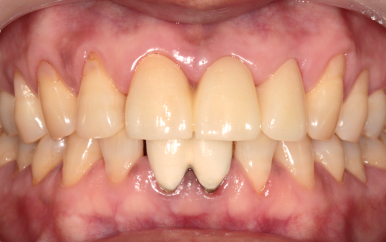

남아 있는 앞니의 신경치료를 안전하게 마무리 한 모습

이후, 뿌리만 남은 치아는 발치를 하였고, 잇몸이 회복되는 동안

양옆의 치아를 신경치료 진행하였습니다.

치아에 금이 가있던 치아는

치아머리 부분의 안정화를 위해 "포스트 Post"라는 과정까지 진행하였습니다.